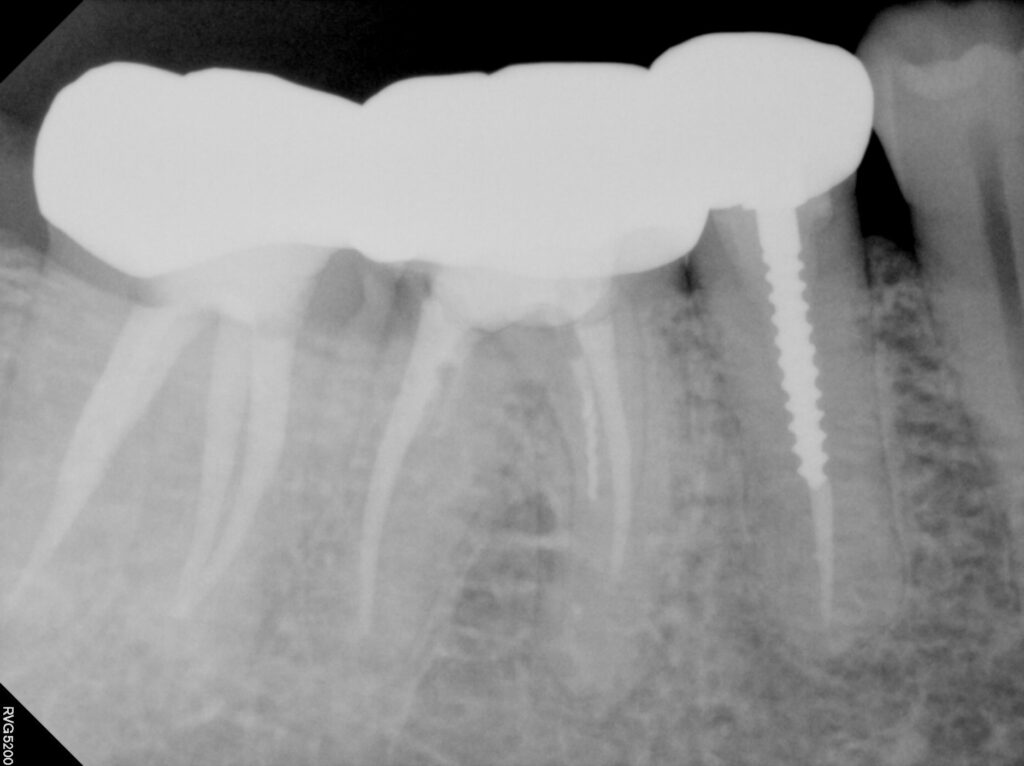

최종적으로 지르코니아 크라운으로 씌워서

치료를 마무리 하였습니다

저는 포기하려고 했지만

환자분의 의지로 자연치아살리기 마무리까지

올 수 있었던 사례입니다